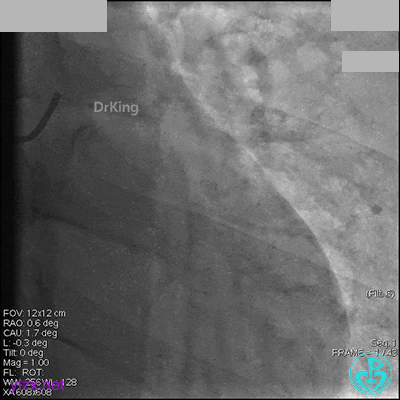

冠脉造影

入院次日冠脉造影显示粗大左主干末端中度狭窄,前降支开口严重狭窄,回旋支与前降支角度大,弥漫性长病变,严重狭窄,粗大右冠脉近中段弥漫性中重度狭窄。由于病变复杂,造影结束后先下台,择期再行介入治疗。